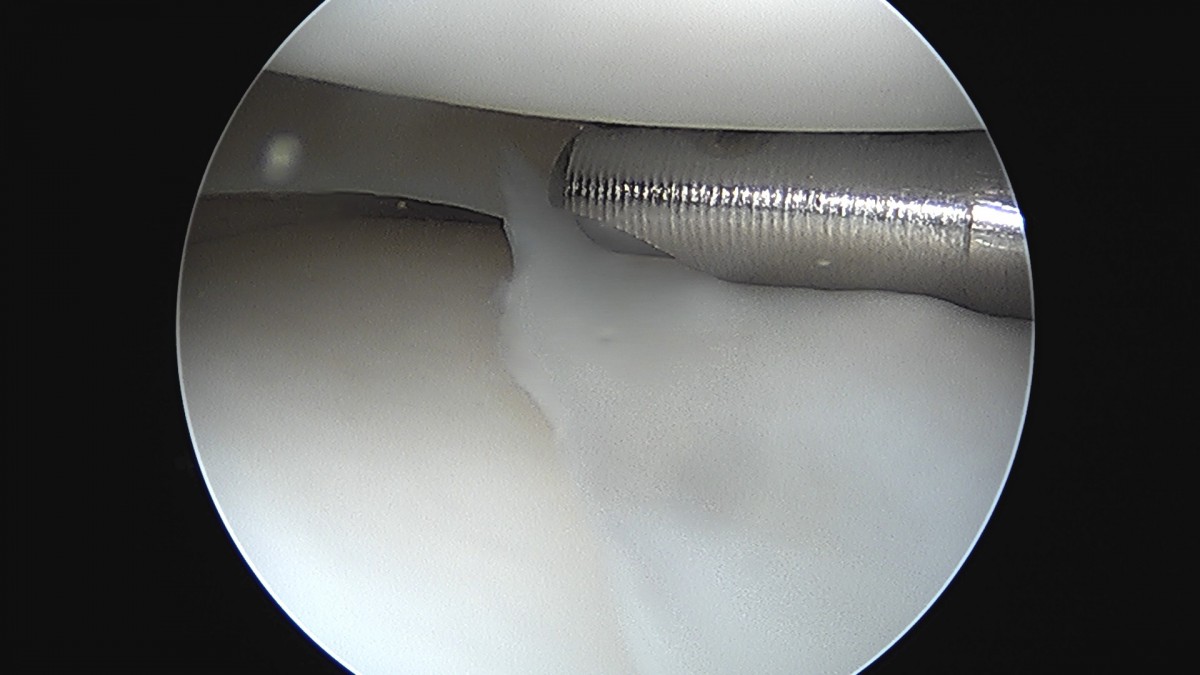

이재상원장님 무릎 반월상 연골판 절제술 김건O 환자

dae765e4d9ac96aee867c9d6292d8784_1758006493_453.jpg